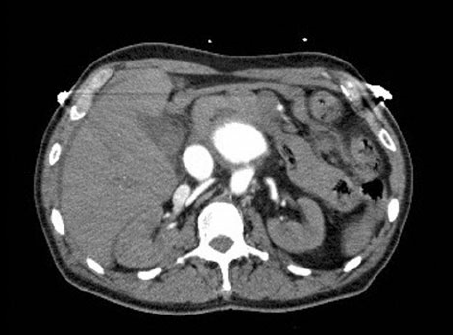

3.2 Digitally Reconstructed Radiographs (DRRs)

Synthetic radiographs were generated directly from CT volumes using the Siddon ray-tracing algorithm, implemented in the open-source DiffDRR framework Gopalakrishnan and Golland (2022). Siddon projection computes exact line integrals through the CT volume, avoiding interpolation artefacts and preserving small, high-density structures such as calcifications. For each scan, we simulated posterior–anterior (PA) and lateral (LA) projections under a fan-beam geometry with fixed source–detector distance (1085.6 mm) and detector width of 512 pixels at 1 mm spacing. Both PA and LA projections used identical source–detector parameters, with the LA view generated by a rotation around the cranio-caudal axis to approximate orthogonal orientation. DRRs were normalised to and resized to . This pipeline yields synthetic radiographs that approximate clinical CXRs while retaining precise CAC labels inherited from the source CTs.